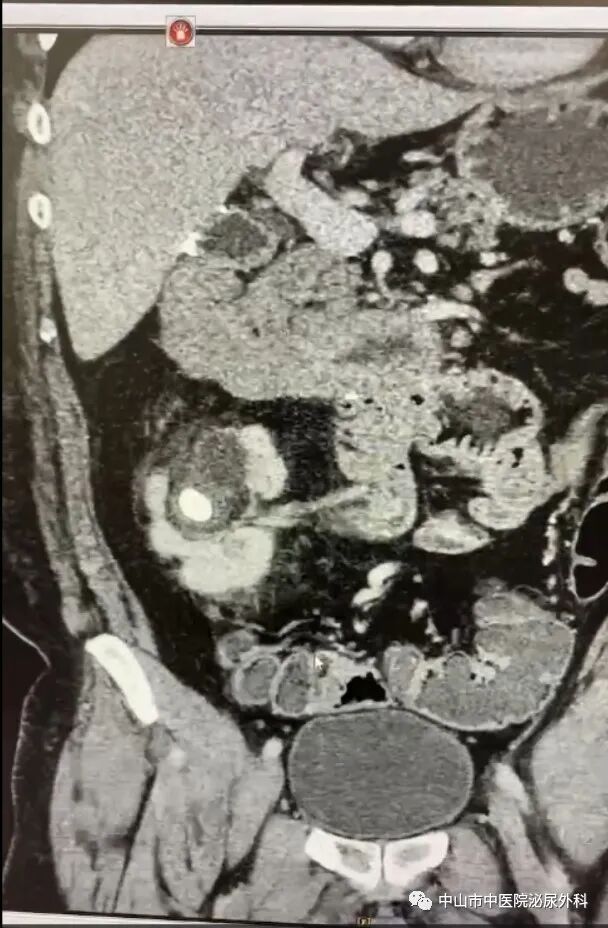

术后复查KUB

输尿管鞘是什么一期软镜治疗罕见交叉异位肾并结石(术中使用一次性末端可弯负压清石鞘)_https://www.jmylbn.com_新闻资讯_第5张